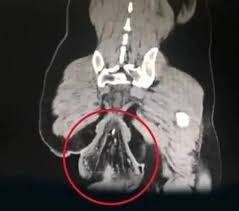

Homem sofre prolapso retal após passar mais de 30 minutos no vaso usando celular Leia mais » 21 de julho de 2025